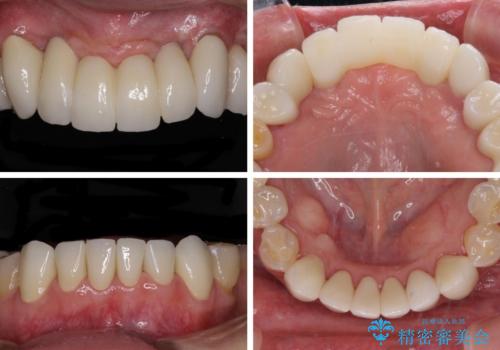

歯周外科処置を行ったことで歯周ポケットはなくなり、毎回のブラッシングの度に嫌な思いをしていた出血は認められなくなりました。

上下前歯の見え方を気にされており、歯だけをみると大変長くなりましたが、笑ったときの口元は自然な外見となり、患者様には大変満足していただきました。